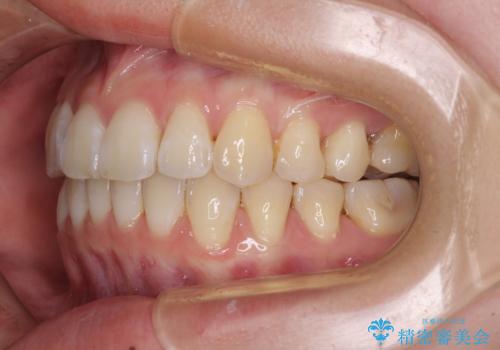

- 海外留学の予定があるが、学生のうちに歯列を整えたいとのことで来院された患者様です。

前歯にデコボコがあり、口元がやや突出した印象があったため、IPR(歯と歯の間を削る)と親知らずを抜歯した上での歯列全体の後方移動をメインに、インビザラインを用いて矯正治療を行うこととしました。

年に一度、夏休みの時期にしか帰国できないため、帰国のタイミングに合わせてマウスピース交換スケジュール治療計画としたため、3年半という期間を要しました。

留学先でもしっかりとマウスピースの装着を実践してくださったので、ご本人の満足のいく仕上がりとなりました。